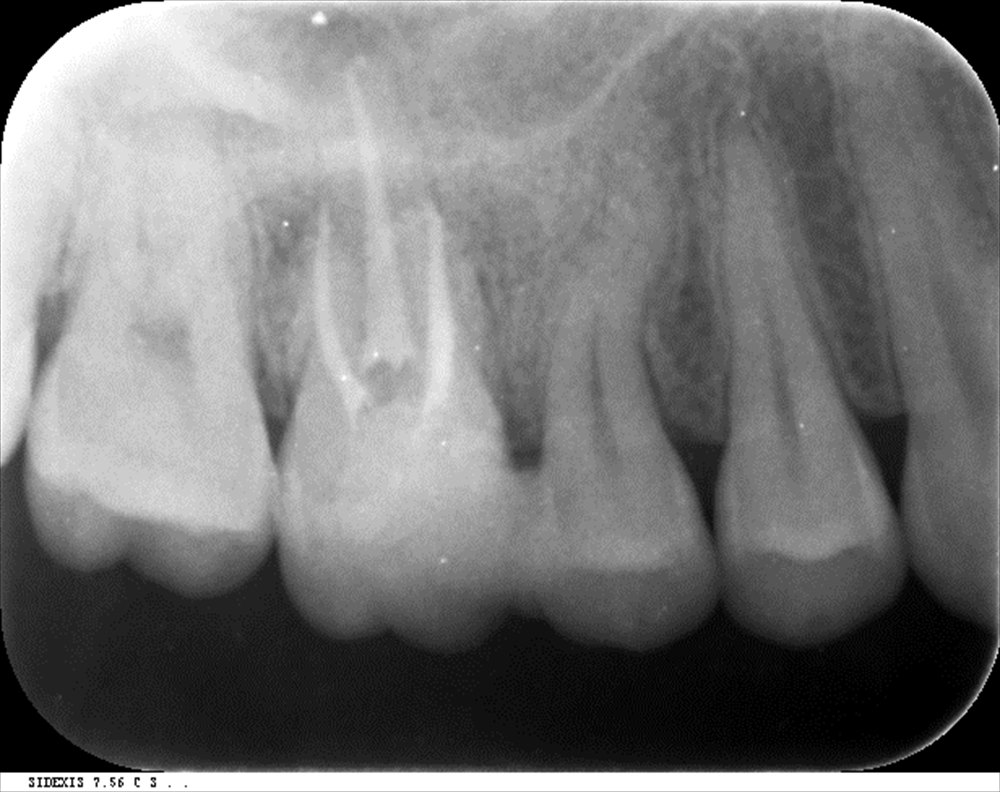

今日のご紹介

右側は痛みを訴え来院時。歯茎から膿が飛び出しています。

左は今日。何もなくなりました。

今日 スタート時2月

症状も消えました。

本日根管充填